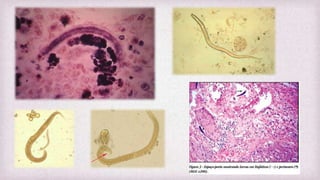

Strongyloides stercoralis

Características gerais

 Pequenos nematódeos de vida livre

 Causa parasitismo intestinal grave

em imunossuprimidos

 Habitat: criptas da mucosa

duodenal e porção superior do

jejuno.

 Fêmea partenogenética mede cerca

de 2 a 3 mm de tamanho

 Doença: ESTRONGILOIDÍASE